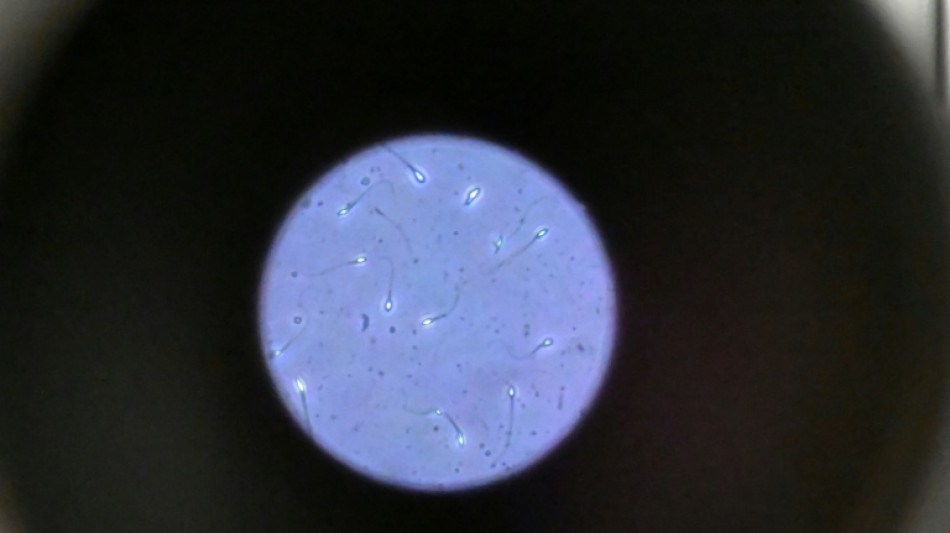

Dans l'espace, les spermatozoïdes ont du mal à trouver leur chemin / Photo: Damien MEYER - AFP/Archives

Dans l'espace, les spermatozoïdes ont du mal à trouver leur chemin vers l'ovule en raison de la microgravité, qui perturbe aussi le développement des embryons, selon une étude publiée jeudi dans Communications Biology.

Les chercheurs ont testé successivement du sperme de souris et humain dans ce dispositif placé dans un appareil en constante rotation pour simuler la microgravité.

Les gamètes ont été environ 50 % moins performants pour naviguer à travers ce parcours que sous la gravité terrestre. Cela équivaut à une baisse de 30% du taux de fécondation réussie, selon les résultats de l'étude.

Les spermatozoïdes ayant réussi à franchir le parcours semblaient produire des embryons de meilleure qualité.

Il semble que le stress lié à la microgravité ait agi comme un "filtre" éliminant les plus faibles et "ne laissant en lice que les plus performants", ce qui pourrait s'avérer "bénéfique", selon Mme McPherson.